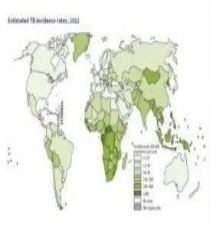

我们都知道结核病是一种严重危害人类健康的慢性传染性疾病。那么结核病流行现状如何呢?我们国家是结核病高负担国家,结核病疫情形势依然严峻,最新世卫组织《2023年全球结核病报告》年报显示,我国2022年新发结核病病例数74.8万,低于印度(27%)和印度尼西亚(10%)位居世界排名第三。